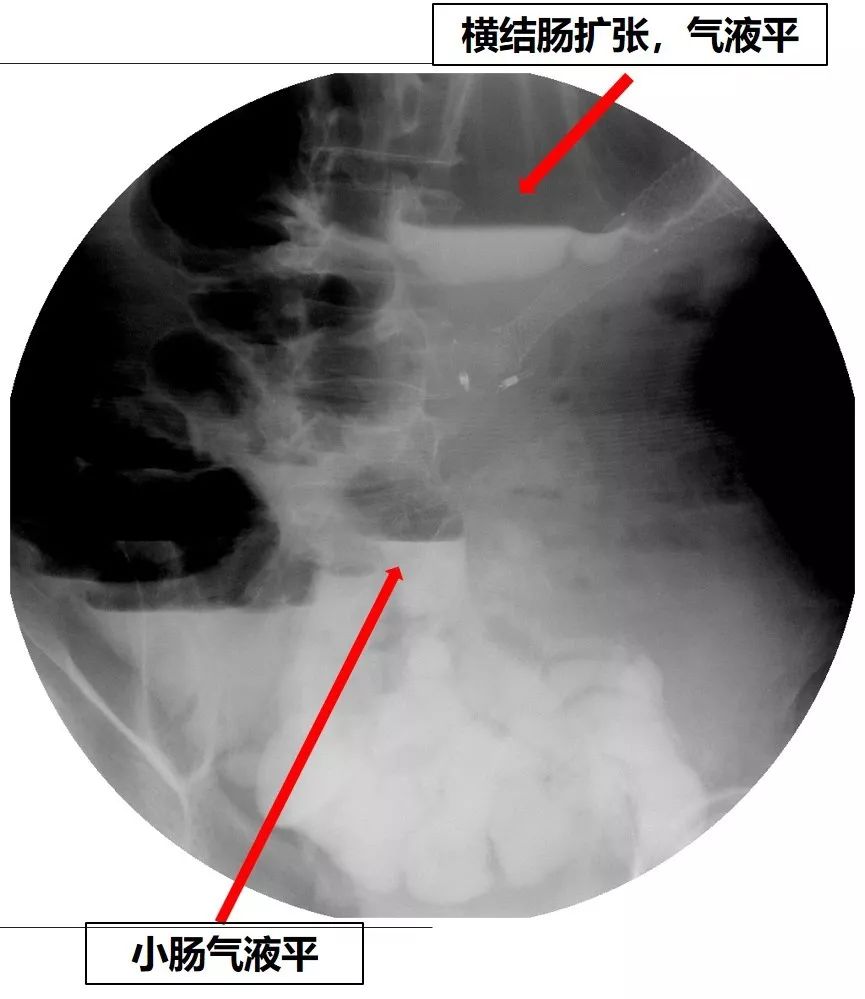

但是患者仍有恶心、呕吐症状,呕吐少量胃液。重新进行全消化道造影,又发现了新的问题:结肠脾曲梗阻!(图21、图22)

图22 消化道造影见肠梗阻--多发的气液平

征得患者及家属同意后,于2019-1-10为患者放置结肠支架。术中结肠镜见结肠脾曲充血水肿,内镜无法通过。未见明确的肿物。结肠支架放置过程顺利,术后复查X线平片,见扩张的结肠回缩,造影剂通过了结肠脾曲(图23)。